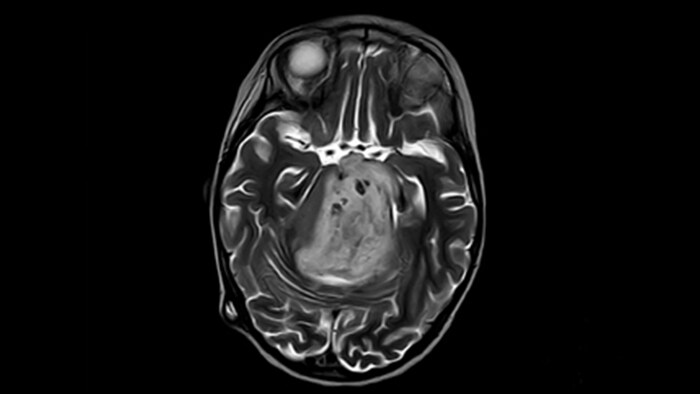

“We have been very, very pleasantly surprised by the quality of the images,” says Dr. Mahajan. “I have shown Prodiva images to people around the world during my travels.” Ingenia Prodiva 1.5T includes such features as dStream digital broadband technology to increase image quality with high SNR. “The system came with its newest sequences that allow us to perform advanced techniques like excellent diffusion in the brain and other body parts as well, spectroscopy, detailed neurography, CSF flow studies, imaging of difficult areas like skull base, tractography, DTI, and even DTI of the spinal cord – all of this is available to us.” The radiologists at Mahajan Imaging were also impressed by the quality of cardiac MRI. “We have done some MR angiography of the coronary arteries with the Prodiva and it provided excellent coronaries – and this was without using any contrast agent. We can also perform fantastic ngiography of other body parts.” “With Prodiva 1.5T, the images are very crisp and sharp, and the resolution is very good,” says Dr. Mahajan. “Imaging can be done in short scan times with excellent quality and broad range of possible applications, whether it is angiography, a scan with 3D reconstruction, any kind of more special images, what we do, the sharpness, resolution and the ease of use – everything counts in total when we are reporting.”